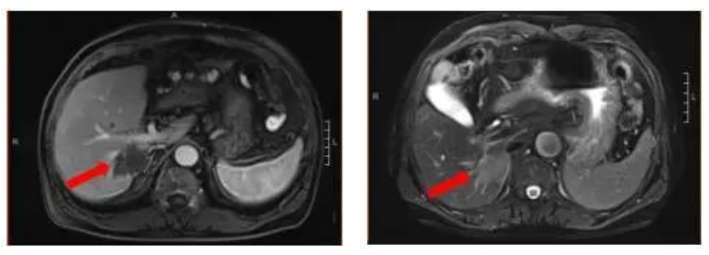

腹部增强MRI:胃壁增厚并腹腔内多发肿大淋巴结(较大者直径约2.6cm),考虑胃Ca并淋巴结转移;肝内多发异常信号灶,考虑转移瘤,6.4*7.8cm。

图1 腹部增强MRI